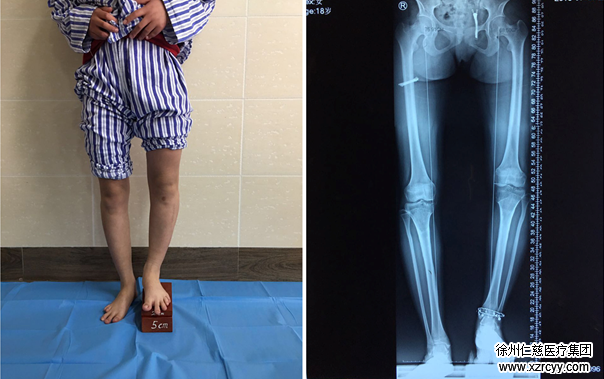

左右腿相差7厘米

接诊的betway在线登陆骨科医生徐明亮检查后发现“双下肢全长X线片显示,左胫腓骨畸形明显。”一测量,婷婷的左下肢较右下肢短7cm。综合考虑后,徐医生给出了治疗建议“应用Ilizarov技术做肢体延长术,能帮助婷婷延长左胫腓骨长度,达到左右腿长度一致的效果。”

(图为双下肢全长X线片)